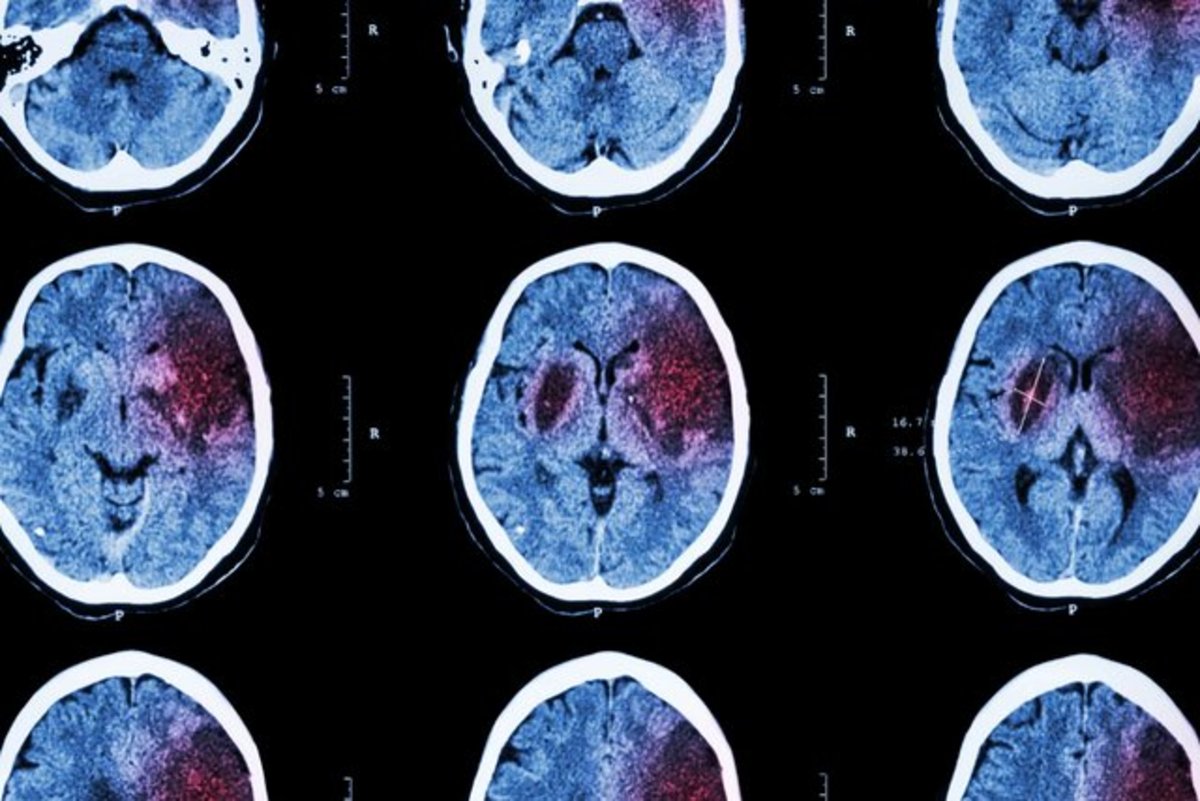

دارویی که می‌تواند به توانبخشی پس از سکته مغزی کمک کند

بررسی جدید پژوهشگران "دانشگاه ایالتی اوهایو" نشان می‌دهد که یکی از دارو‌های اختلال عصبی می‌تواند به توانبخشی پس از سکته مغزی کمک کند.

سکته مغزی ایسکمیک زمانی رخ می‌دهد که انسداد رگ خونی، جریان خون به مغز را متوقف می‌کند و به از بین رفتن نورون‌ها منجر می‌شود. بازماندگان سکته مغزی ممکن است از اختلال در کنترل حرکت و گفتار و سایر ناتوانی‌ها رنج ببرند و اغلب به توانبخشی بلندمدت نیاز داشته باشند.